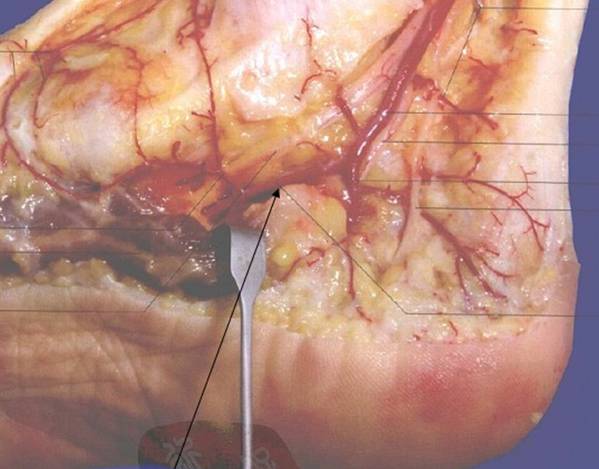

今天讲课

查了些文献

对足内侧皮瓣进行了回顾总结